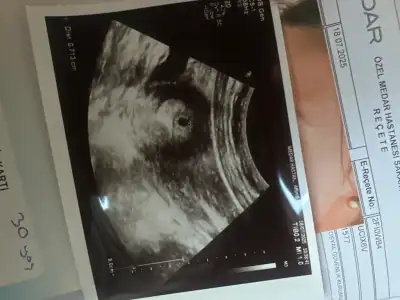

Kizlar keseyi gördük çok minik dedi 7mm dedi 4 haftalikmiş🥹🥹🥹

Eklentiler

• image.webp

image.webp

33,1 KB · Görüntüleme: 78